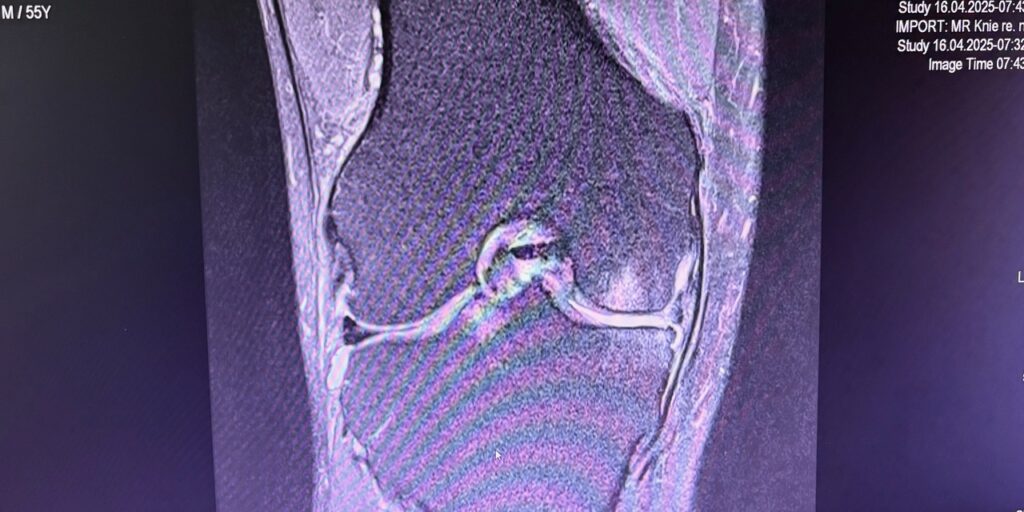

Η ημιολική αρθροπλαστική γόνατος (partial / unicompartmental knee replacement) είναι επέμβαση όπου αντικαθίσταται μόνο το φθαρμένο διαμέρισμα του γόνατος και όχι ολόκληρη η άρθρωση.

- Άθικτοι σύνδεσμοι (κυρίως πρόσθιος χιαστός)

- Καλή κινητικότητα γόνατος

- σωστή διάγνωση

- εμπειρία χειρουργού

- ακριβή τοποθέτηση (συχνά με ρομποτική υποβοήθηση)